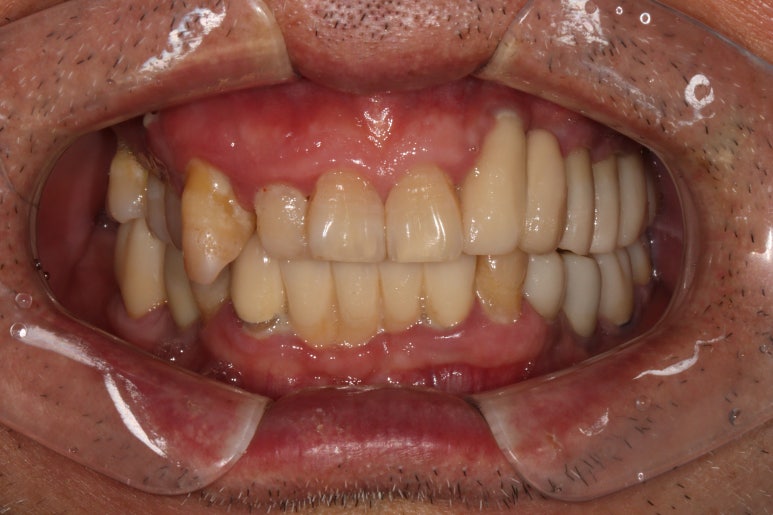

1주일 뒤에 제작된 앞니 지르코니아 브릿지입니다.

제가 봐도 좀 잘되었다고 감히 말할 정도로 완벽한 모습입니다....

사실 딱 보면 브릿지인지도 잘 모르겠네요...

바로 요기가 새로 제작한 지르코니아 앞니 브릿지입니다.

감쪽같은 앞니 치료 아니겠습니까!! 크... 제가 봐도 칭찬합니다.

입천장에서 바라보면 이제 가지런히 정렬되어있는 치아의 배열을 보실 수 있으실겁니다.

앞니 지르코니아 브릿지 접착 후 치과용 파노라마 사진입니다.